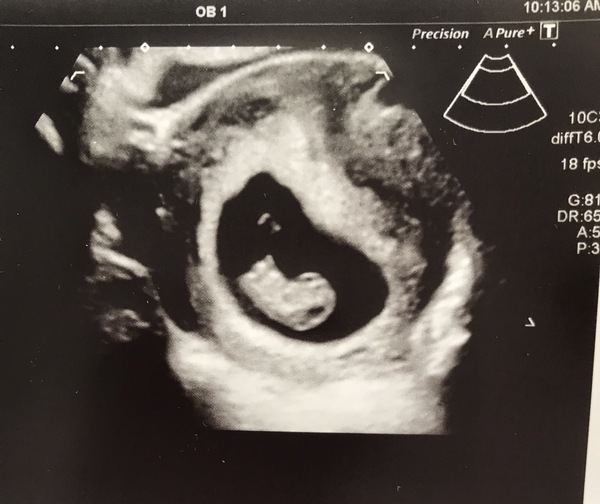

Thankyou all. All ok, heartbeat found and measuring slightly ahead at 9 weeks. They even booked in my 12 week scan for me while I was there. 15th May. I can relax a little now! Picture of blob attached. I may just let myself believe it’s real now!